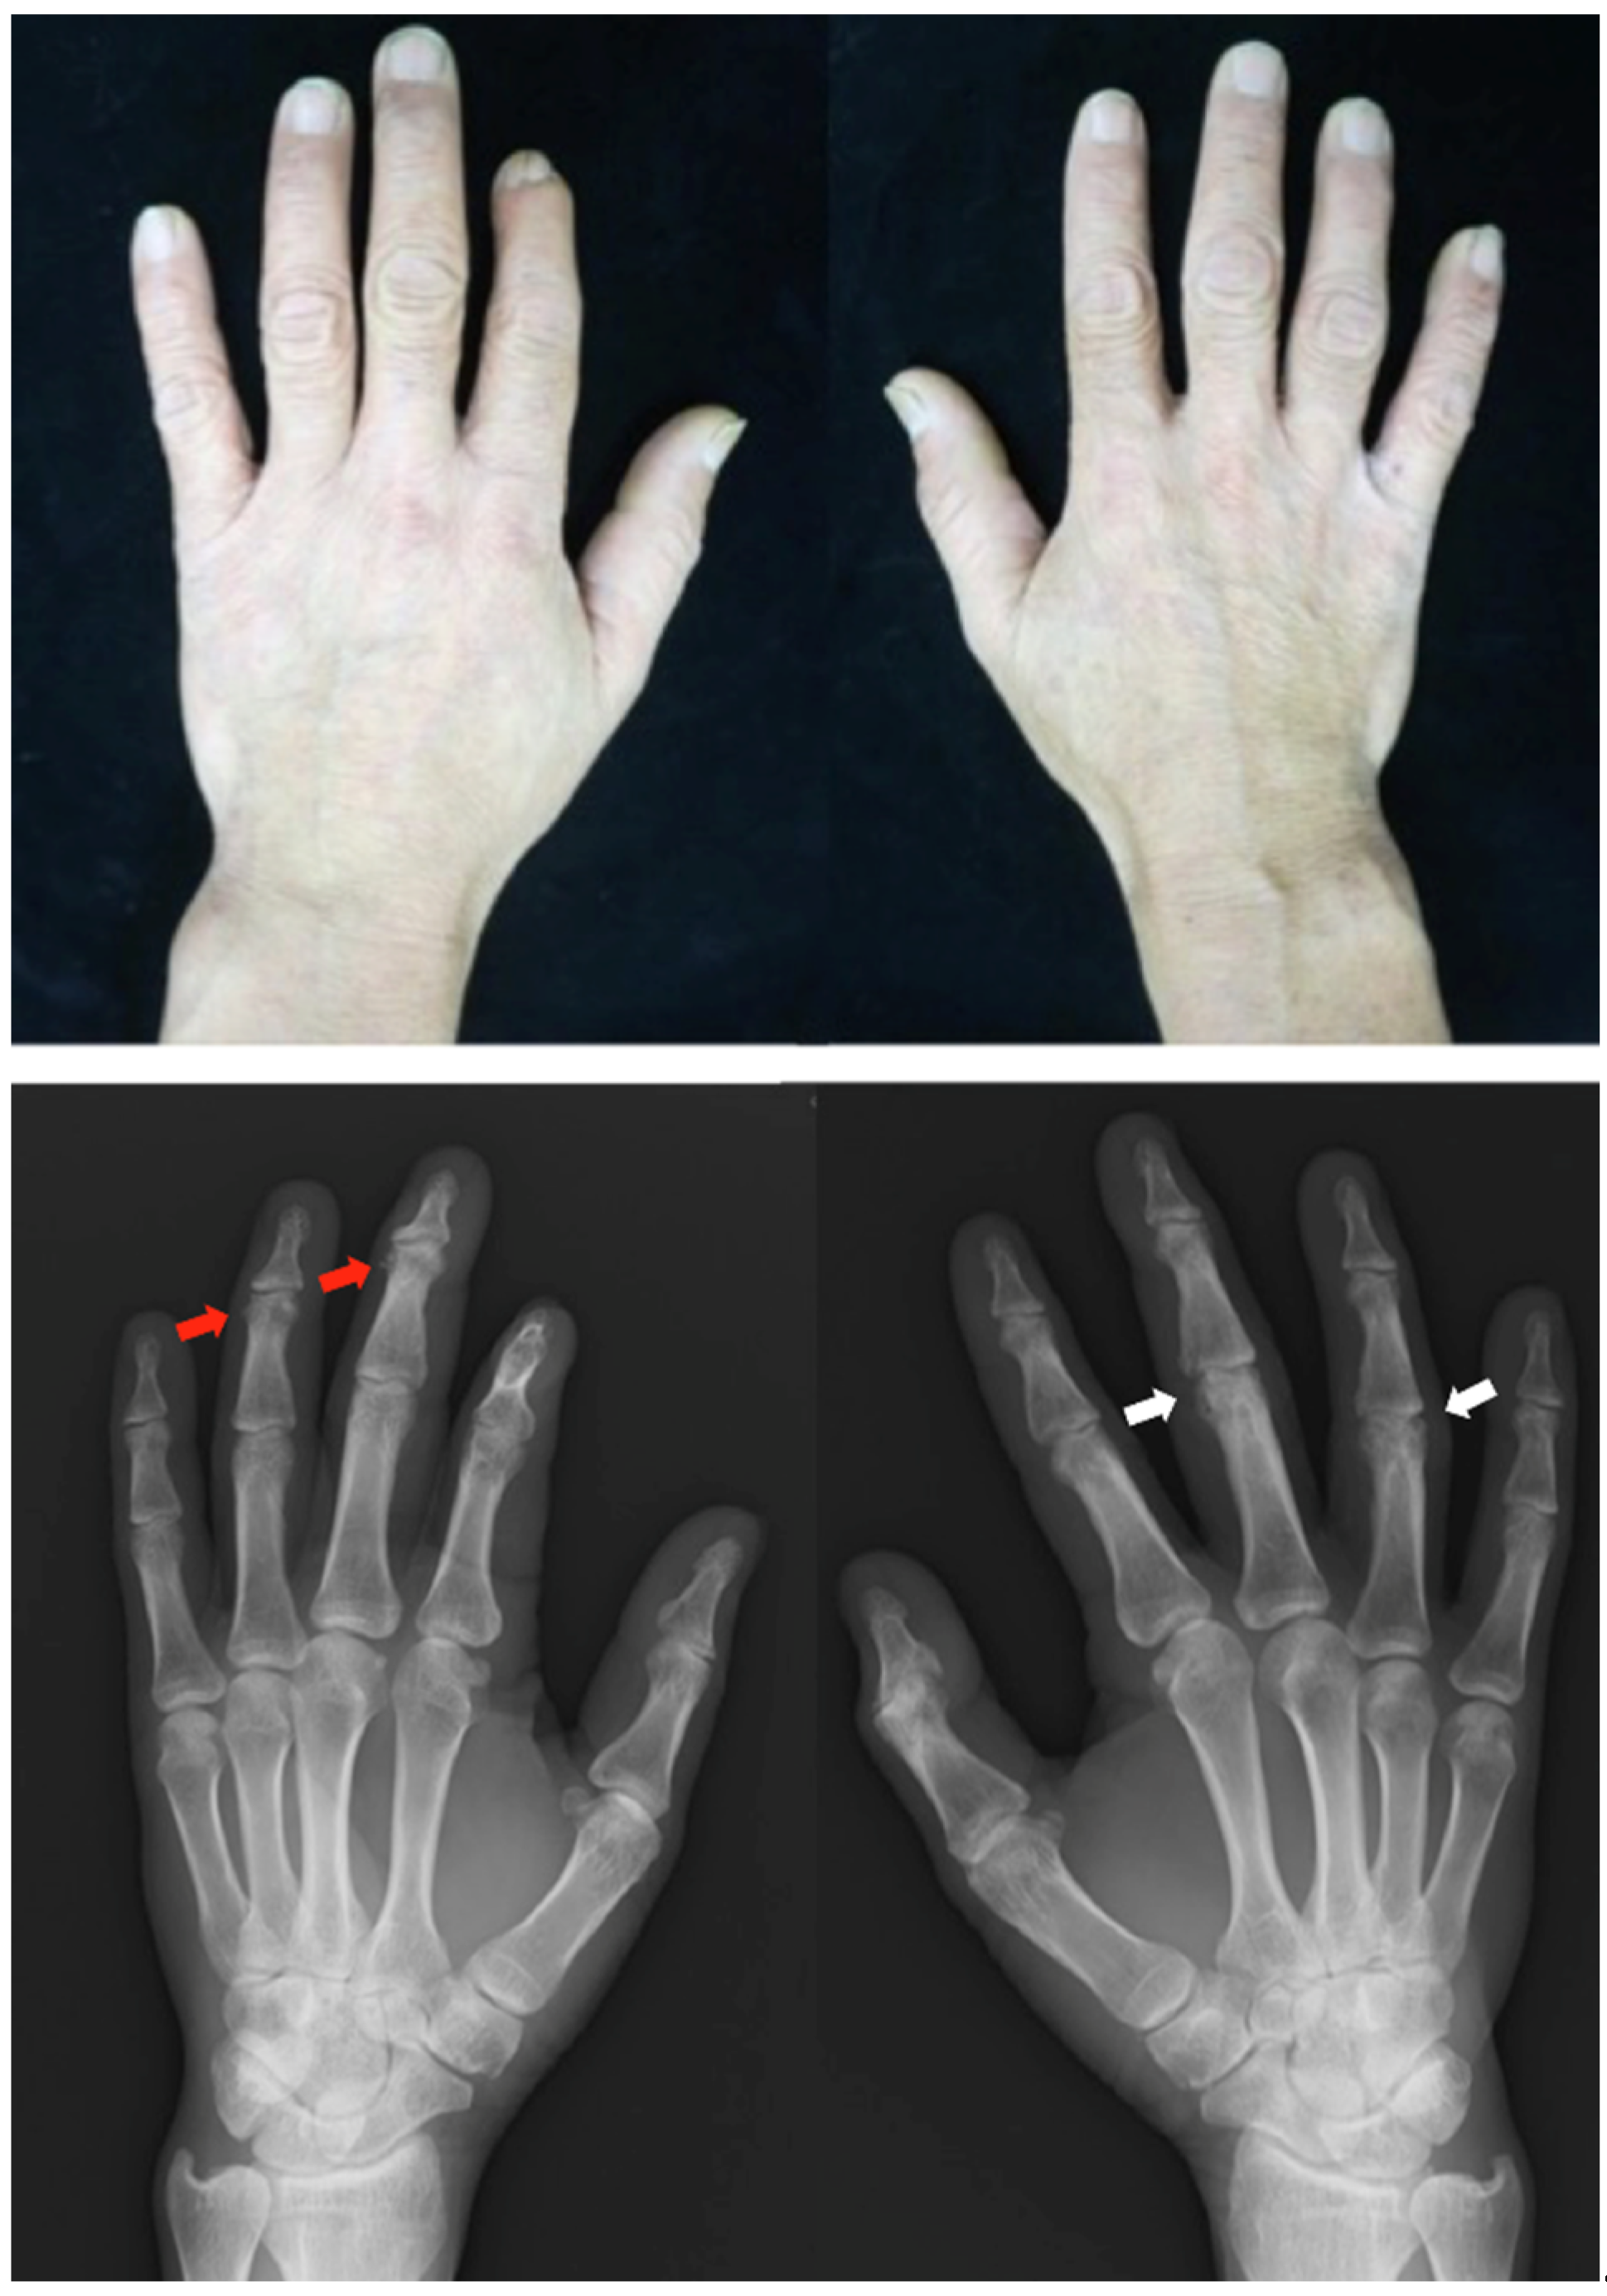

Clinical findings: During treatment with adalimumab, there was no psoriatic rash, but she had pain in her hand joints, wrists, and knee. Both ACPA and RF values were negative as long as adalimumab was effective; however, when adalimumab became ineffective, both ACPA and RF values were positive with high titers. Radiographs showed bone erosion, a radiolucent shadow, joint destruction in the hand’s MCP, PIP, and DIP joints, bone erosion in the wrist joint, and subluxation of the MCP joint in the ulnar direction (Figure 5).

Figure 5.

Clinical photographs and radiographs of the hands in case 5. Right-hand fingers show mild ulnar deviation. On the radiographs, the MCP joints are subluxated symmetrically. Radiographs show bone erosion, narrowing joint space, and destruction in both hands’ MCP, PIP, and DIP joints. MCP, metacarpophalangeal; PIP, peripheral interphalangeal; DIP, distal interphalangeal.

Clinical findings: The patient had psoriatic plaques on the scalp, lower legs (PASI score: 9.8), and ankle and hand arthralgia. Onycholysis was observed on his hand nails. Radiographs of the hands showed narrowing of the joint space and destruction in the DIP and PIP joints (Figure 7).

Figure 7.

Clinical photographs and radiographs of the hands in case 7. Radiographs show erosions adjacent to periarticular bone proliferation at the collateral ligament and capsular joint attachment site (red arrow). Bone erosions are noted in the right third and fourth PIP joints (white arrow). PIP, peripheral interphalangeal.